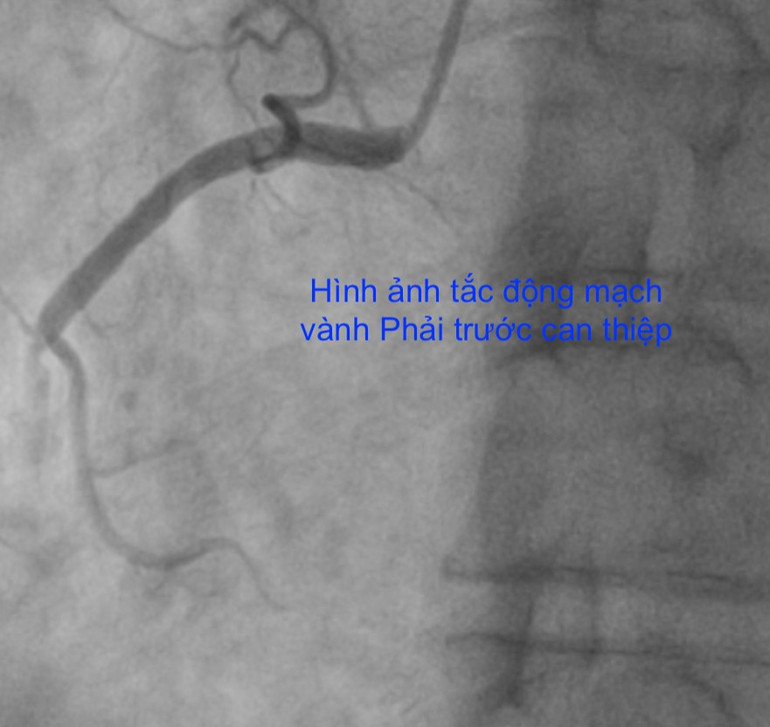

Bệnh nhân nam 67 tuổi (Bắc Ninh) vào Bệnh viện Trung ương Quân đội 108 với tình trạng đau ngực trái dữ dội. Trước đó bệnh nhân nhập viện đa khoa tỉnh với chẩn đoán nhồi máu cơ tim và có tình trạng tụt huyết áp, nhịp chậm, tình trạng nguy kịch, ngay sau đó đã được chuyển đến Bệnh viện Trung ương Quân đội 108.

Tại Bệnh viện Trung ương Quân đội 108, bệnh nhân đã được xử trí cấp cứu chụp mạch vành qua da và đặt stent tái thông động mạch vành thủ phạm gây nhồi máu cơ tim.